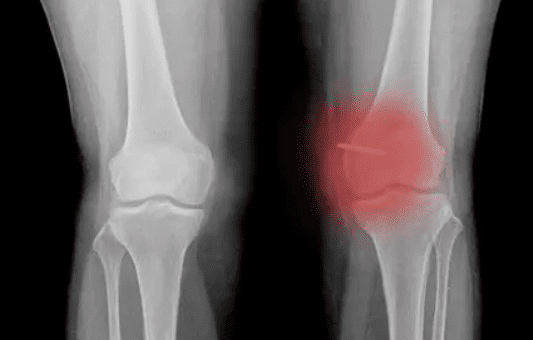

骨骼的發育是很重要的,如果骨骼發育不好的話會影響健康。骨密度低是骨骼發育最常見的一個問題,那么骨密度低是怎么造成的?該怎么辦呢?

一般情況下,骨密度低是不利于身體健康的。骨密度低形成的原因有很多,比如營養攝入不均衡、年齡因素、運動不足以及內分泌失調等因素。下面讓我們具體來看看骨密度低是怎么造成的吧!